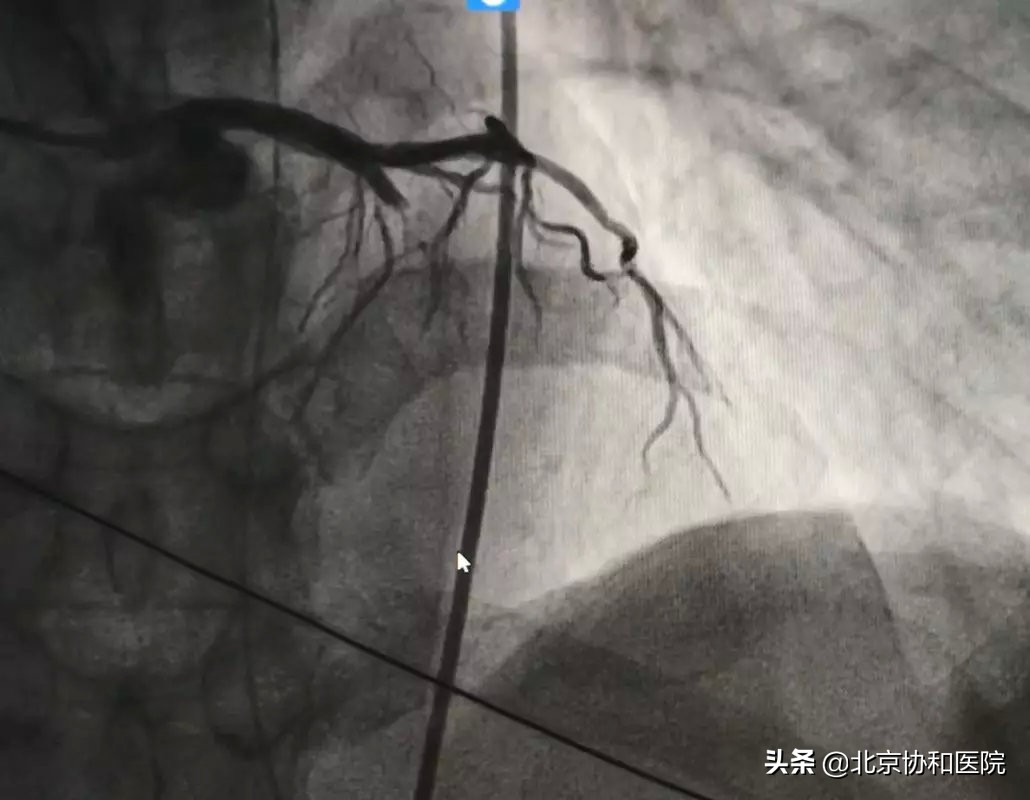

导管室准备就绪且通知转运病人。董先生在急诊科医护的陪同下被转入心内科导管室,由刘震宇医生进行急诊冠脉造影和急诊PCI(经皮冠状动脉介入术)。冠脉造影显示患者前降支近端完全闭塞,植入支架后血管恢复畅通。术后收入CCU(冠心病重症监护室病房)进一步治疗。

放置支架前(左图)后(右图)对比—前降支远端血管畅通 图/王江山